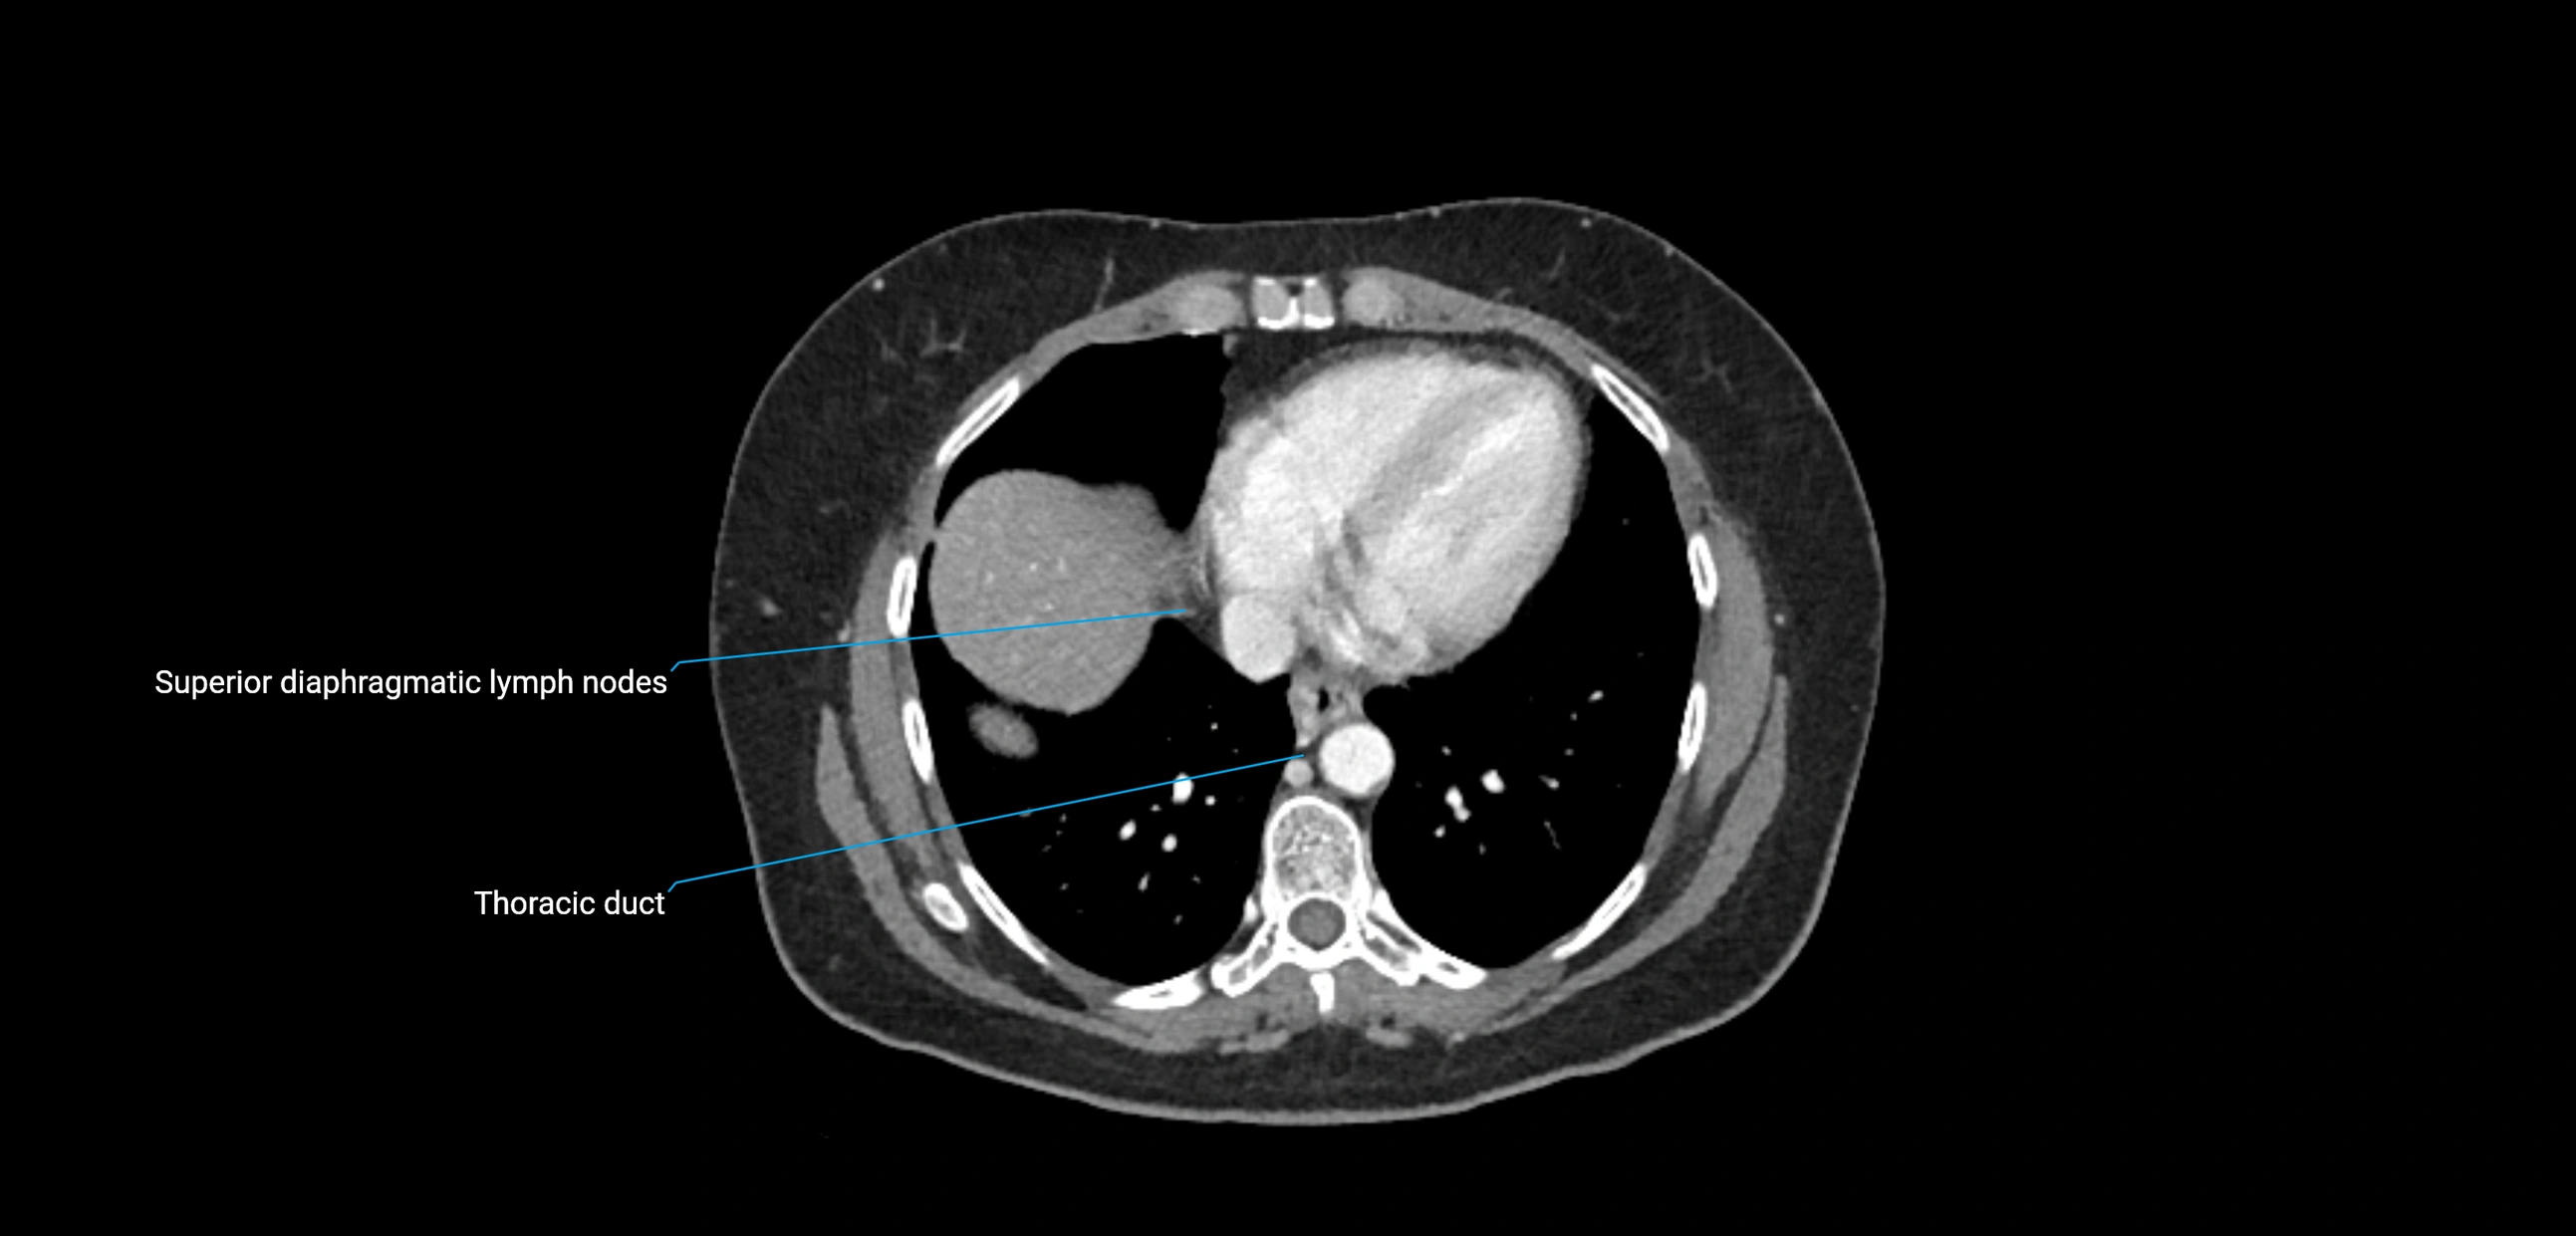

These nodes receive lymph from a wide range of abdominal and pelvic structures. Specifically, they drain lymph from the kidneys, suprarenal glands, gonads (testes/ovaries), uterus, uterine tubes, and pelvic organs, before converging into the lumbar lymphatic trunks, which terminate in the cisterna chyli → thoracic duct.

• Provide a major pathway to the cisterna chyli and thoracic duct

CT Appearance

CT Pre-Contrast:

• Nodes appear as soft-tissue density nodules adjacent to the aorta and IVC

CT Post-Contrast:

• Normal nodes enhance homogeneously

• Malignant nodes may show heterogeneous enhancement, central necrosis, or conglomerate formation

• Size >1 cm short axis is suspicious, though morphology and distribution are equally important

CT image

image